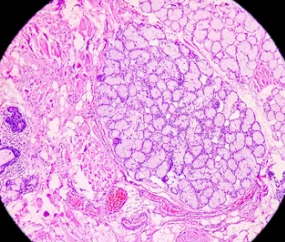

- 조직 검사: 구강 검진에서 암 의심 부위가 발견되면 조직 검사를 시행합니다. 혀의 일부를 떼어내 현미경으로 검사하여 암세포 유무를 확인합니다. 조직 검사는 혀암 확진에 필수적인 검사입니다.